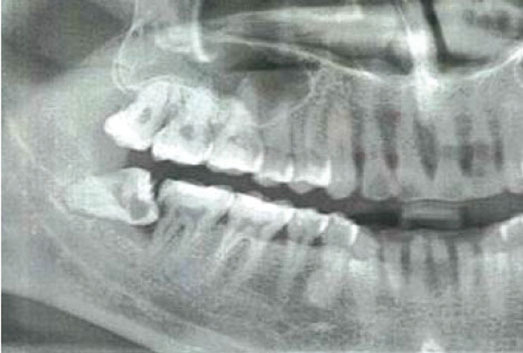

경부심부감염의 발생 원인과 시점은 제출된 진료기록, 파노라마 영상, 신청인의 경위서, 피신청인의 답변서 등의 자료로는 정확히 추정하기 어려우나, 파노라마 영상에서 보이는 #48 치아의 맹출 경사도 및 골 흡수양상, 치아우식이 관찰되는바, #48 치아 주변의 만성적인 수평지치주위염 가능성이 높은 것으로 판단되며, 이러한 만성염증이 경부심부감염의 발생 원인으로 추정됨. 발생 시점은 #48 치아의 통증이 발생된 시점 또는 발치 전·후로도 판단할 수 있으나, 발치 전 CT 등 악안면 영역의 감염정도를 판단할 수 있는 자료가 없어 정확히는 추정할 수 없음. 또한, 경부 심부감염 발생은 #48 수평지치 발치보다 #48 치아 주변의 만성 주위염으로 추정되는 만성염증의 진행과정과 인과관계가 높은 것으로 보이며, 이 시기에 사랑니 발치가 이루어져 만성 염증 진행과정이 다소 심화된 것으로 추정됨.